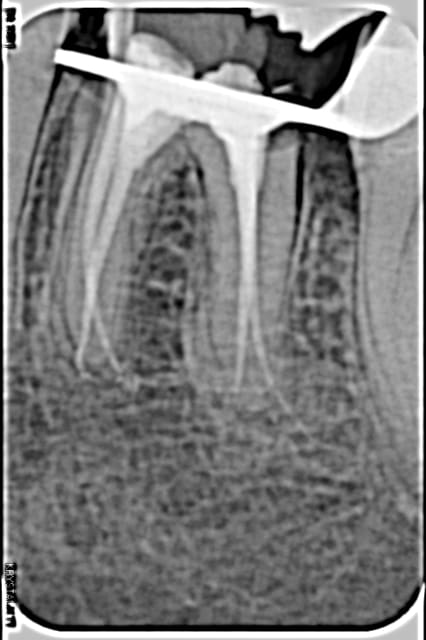

Petite endo bizarre...

Endo 17  2  c nes xyk9ig - Eugenol

Endo 17  3  postop iprbqy - Eugenol

Endo 17  1  preop n6m5ub - Eugenol